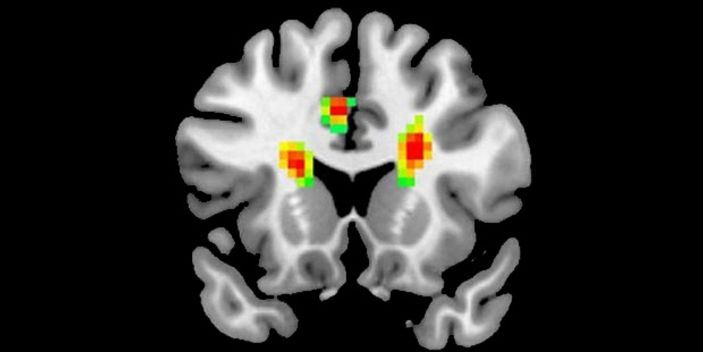

Aşık insanların beyin MR'ı çekildi(Aşık olan bir insanın beyni)

Araştırma sonucuna göre, aşıkken beynimize giden kan miktarı artıyor ve beynimizin 12 bölgesi aktif oluyor. Beynin önde gelen fonksiyonel değişiklikleriyle ilgili ilk amfirik kanıtını gözler önüne seren araştırma, aşkın insanlar üzerindeki etkilerini tam olarak açıklığa kavuşturmasa da işe bir yerlerden başlıyor.

MR görüntülerine göre aşık olduğumuzda korku kontrolü, muhakeme, negatif duyguları kontrol etme ve empati gibi yeteneklerimizi geçici olarak kaybediyoruz. Beyin dalgaları üzerinde yapılan araştırmaya göre tutkunu olduğumuz birine baktığımızda değerlendirme yapabilme yeteneğimizi geçici olarak kaybediyoruz.